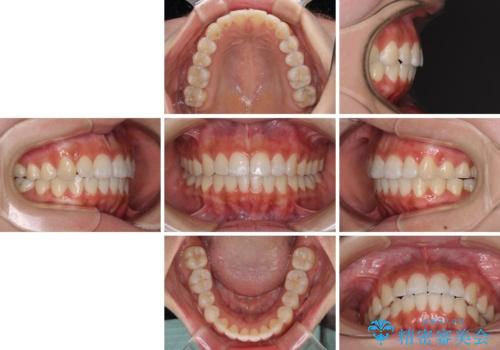

- 上下前歯のデコボコを気にして来院された患者様です。

インビザラインによる上下歯列の拡大と、IPR(歯と歯の間を削る)にるスペースの獲得により、前歯のデコボコを改善することとしました。

しっかりと装着時間を遵守してくださったので、思い通りの歯列に整えることができました。

結婚式前に終了させることができ、患者様には大変満足していただきました。